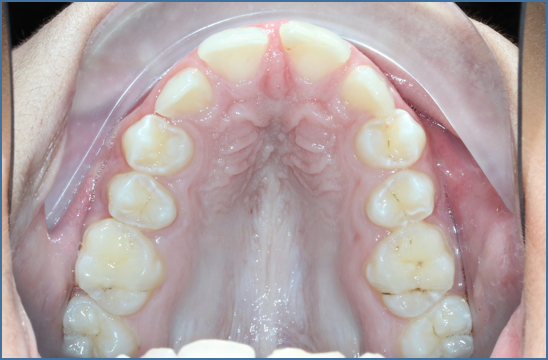

Upper Removable Appliance (URA) expansion brace. Used in a growing children, usually in pre-teenage years before all ‘adult teeth’ have erupted and whilst ‘baby teeth’ are still present, to orthodontically expand the upper teeth within their supporting upper jaw bone

alt="narrow dental arch"

Before treatment, narrow dental arch with no space for canine teeth